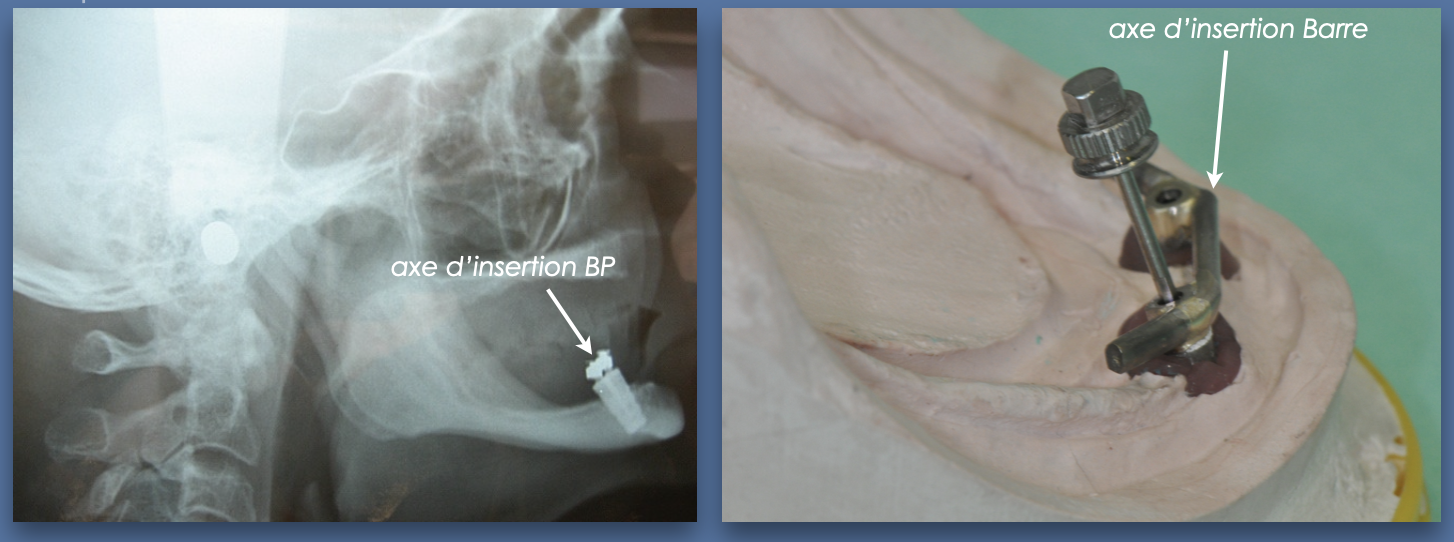

Insertion prothétique difficile

Il arrive que les implants soient placés en émergence relativement linguale pour des raisons anatomiques ou qu’ils ne soient pas parallèles

Dans le cas de boutons-pression (qui sont dans l’axe des implants), un patient peut alors avoir des difficultés à positionner sa prothèse sur les boutons-pression. Cette difficulté peut être insurmontable chez un patient âgé à agilité réduite ou chez un patient nerveux qui risque de détériorer rapidement les parties femelles des attaches !

Il est donc préférable dans ces situations de concevoir une barre : la barre est orientée au laboratoire selon un axe d’insertion prothétique adapté, en l’occurence légèrement vers l’avant :

Le patient est alors beaucoup plus à l’aise pour insérer et désinsérer sa prothèse et les risques de complications mécaniques sont nettement diminués